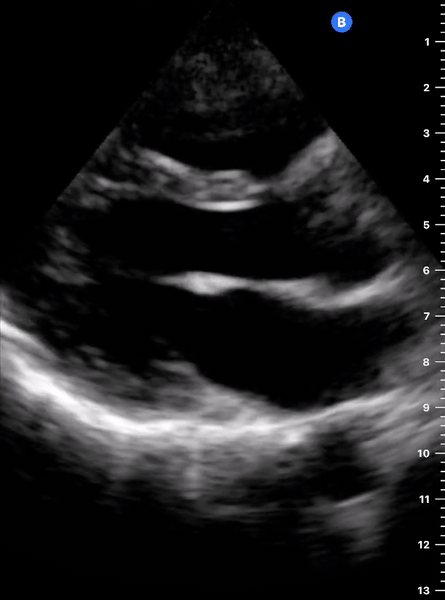

LANDMARKS

A correct PLAX view will align with the heart’s long axis, producing a sagittal cut. On the screen, from the top, we see the right ventricle, the interventricular septum, the left ventricle with its outflow tract, the aortic valve and aortic root, and the left atrium. It is essential to look for the descending aorta, which appears in a transversal cut deeper to the LV.